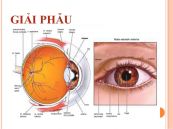

Điện sinh lý bao gồm các thủ thuật khác nhau để đo mức độ hoạt động của võng mạc. Nó có thể giúp kiểm tra các bệnh về võng mạc. Các thủ thuật cũng có thể giúp chẩn đoán và đánh giá các loại vấn đề về thị lực và sức khỏe khác nhau. Để hiểu rõ hơn về thủ thuật này, mời các bạn tham khảo bài viết dưới đây!